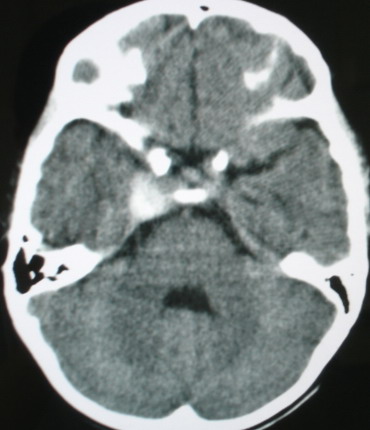

m/8y,右侧眼睑下垂数天,头昏,无呕吐、无外伤史。无搏动性突眼。病人明天来增强。

考虑颈内动脉海绵窦段动脉瘤,建议mri检查。

考虑海绵窦血管瘤,做mri效果比较好。

考虑海绵窦血管瘤,建议mri进一步检查效果。